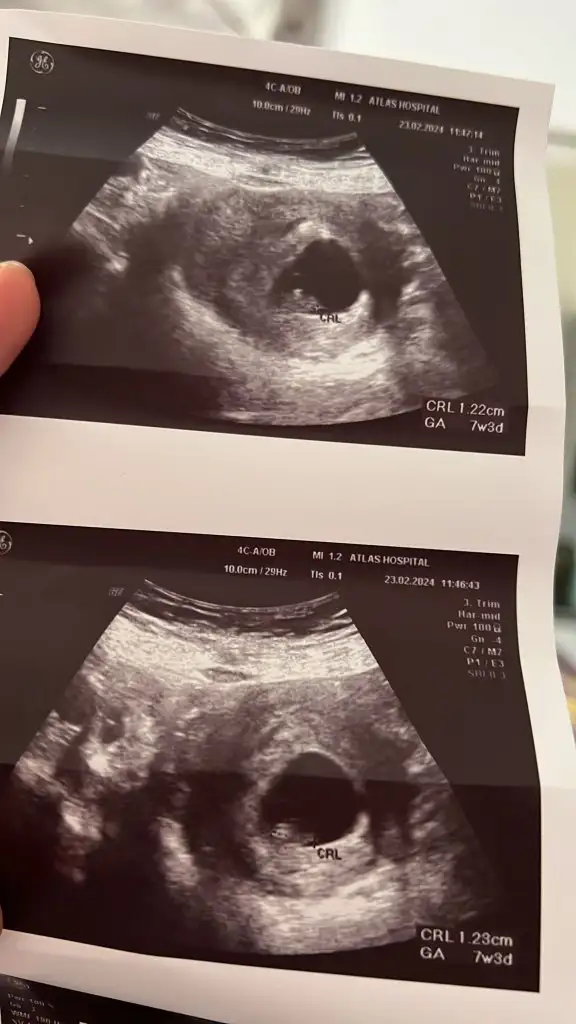

Tabi elimden geldiğinceSelam benim usg de yorumlar mısınız acaba?

7+3 karından bakıldıTabi elimden geldiğince

Burda da 6+ vajinal bakıldıTabi elimden geldiğince

Merhaba tekrar gördüğüm kadarıyla büyük ihtimal kız gibi duruyor tabiki kesin diyemem ama gözlem ve tecrübelerim bu yönde7+3 karından bakıldı

Yüzlerce ultrason görseli görmüş olabilirim sanırım edindiğim tecrubelerden, kesenin şekli ve bulunduğu konumuna bakarak az çok tahminde bulunabiliyorum naçizane:) kızımın ultrasonlari da benzerdi genelde kız oluyor bu konumda ama tabi net drunuz paylaşırNasıl anlıyorsunuz acaba

Vajinal de sağda duruyor o yüzden acaba erkekmidir diye düşündüm aslında tek yumurta ikiziydi ama maalesef birinin gelişimi durduHayırlısı olsun inşallahkimse tahminden sonra teori tuttu veya tutmadı diye yazmamış daha çok küçüğüz öğrendiğimde unutmazsam yazarım

Öyle mi çok üzüldüm ama vardır bı hayır elbet, Allah ahirette kavuştursun ,diğer yavrunuz sizi bırakmamışVajinal de sağda duruyor o yüzden acaba erkekmidir diye düşündüm aslında tek yumurta ikiziydi ama maalesef birinin gelişimi durdu